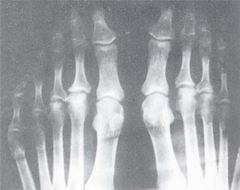

引發關節炎

關節炎風濕性關節炎為風濕熱的表現之一,多見於成年人,常發生於膝、肩、肘、腕等大關節,發病多在上呼吸道感染之後,出現遊走性關節痛、腫及發熱和其它風濕熱的表現。類風濕性關節炎多見於青壯年,起病緩慢,常發生於手足小關節及骶髂部,並逐漸累及全身關節。初始患病關節亦表現出紅、腫、痛及活動不便等,久則關節畸形或強直。外傷性關節炎多因外傷或持續慢性勞損引起關節軟骨發生退行性變或形成骨刺,表現為患病關節腫、痛及運動障礙,易發生在持重關節、如肩、膝、踝等關節,在運動員及青壯年中多見。骨性關節炎由組織變性及積累性勞損引起,多見於肥胖超重的中老年人,最常發病的部位是膝、手指、頸、腰椎等處,症狀主要為關節疼痛、僵硬(經輕微活動後會覺疼痛減輕),重者可出現關節腫脹、肌肉萎縮等。

化膿性關節炎往往由細菌侵入關節腔引起,多見於少年兒童,常發生於髖關節,主要症狀為局部紅、腫、痛、熱和功能障礙,以及高熱等全身中毒症狀。無論何種原因引起的關節炎或何種類型的關節炎,均應及早診治,以免導致永久性關節功能障礙甚至致殘。